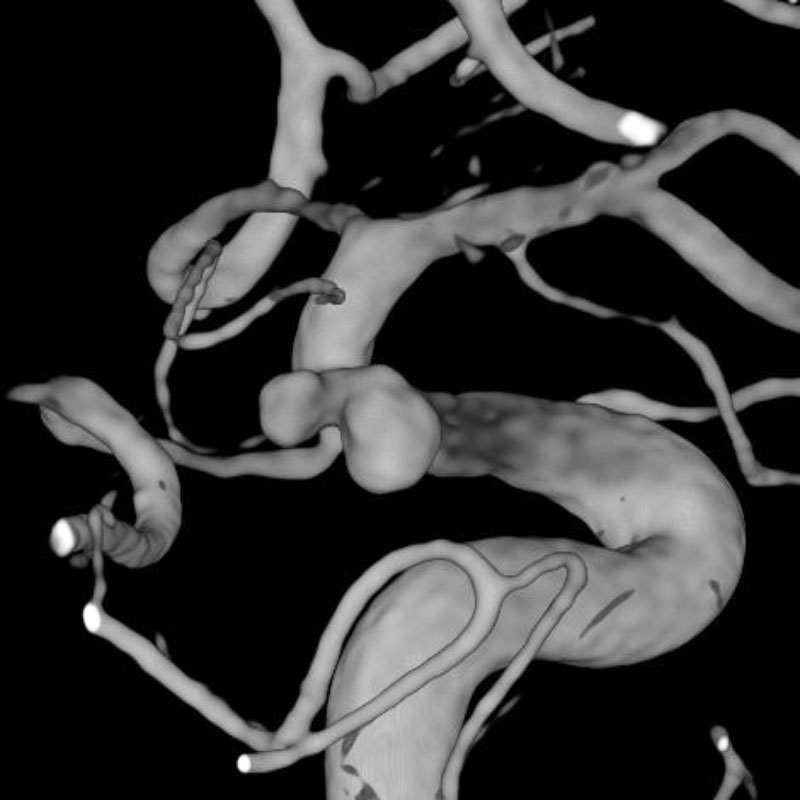

脳動静脈奇形

血管塞栓術

松田/濵田/元永